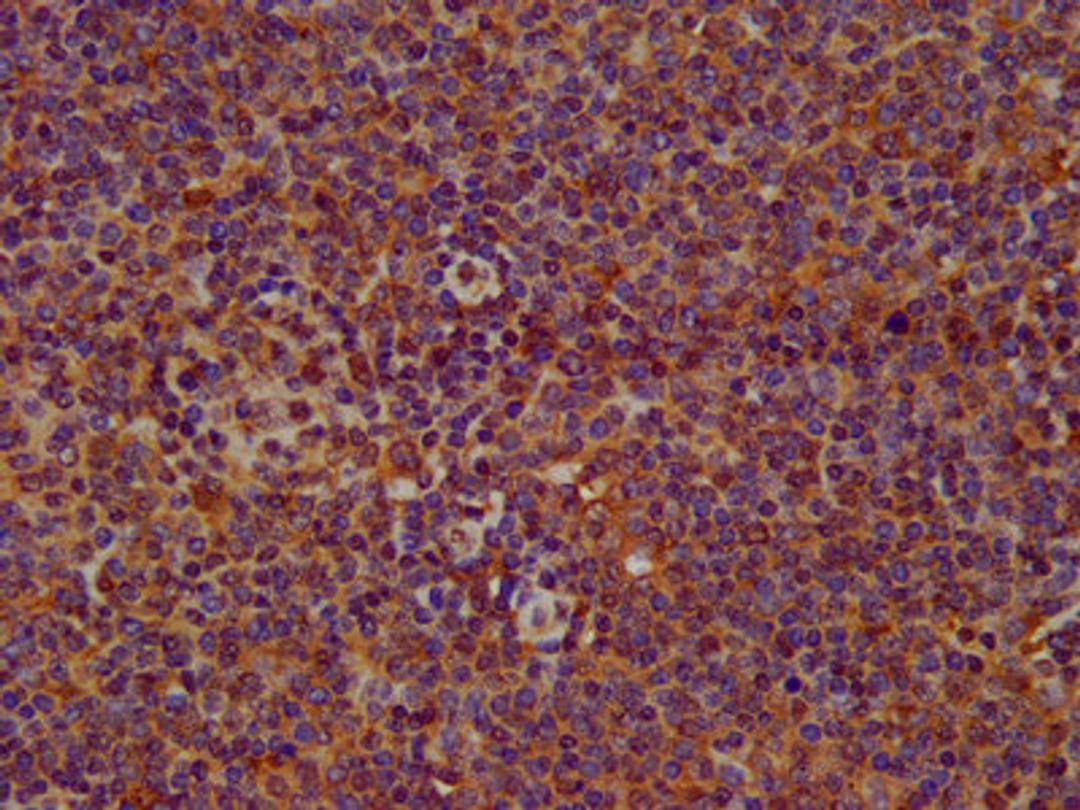

IHC image of CSB-PA822276LA01HU diluted at 1:200 and staining in paraffin-embedded human lymph node tissue performed on a Leica BondTM system. After dewaxing and hydration, antigen retrieval was mediated by high pressure in a citrate buffer (pH 6.0). Section was blocked with 10% normal goat serum 30min at RT. Then primary antibody (1% BSA) was incubated at 4°C overnight. The primary is detected by a biotinylated secondary antibody and visualized using an HRP conjugated SP system.